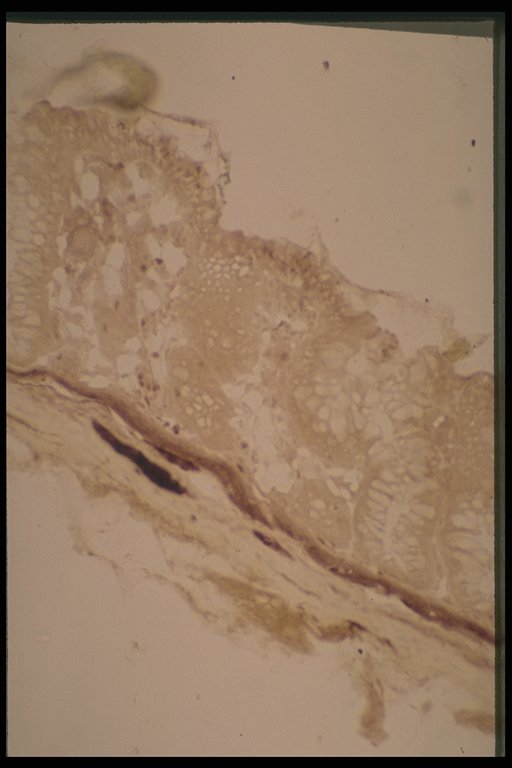

Sometimes, especially in the newborn, only thick nerves with increased acetylcholinesterase activity are demonstrated in the submucosa, a variation that can be accepted as Hirschsprung's disease

Sometimes, especially in the newborn, only thick nerve with increased acetylcholinesterase activity is demonstrated in the submucosa, a variation that can be considered Hirschsprung's disease (LP: lamina propria, MM: muscularis mucosae, SM: submucosa)